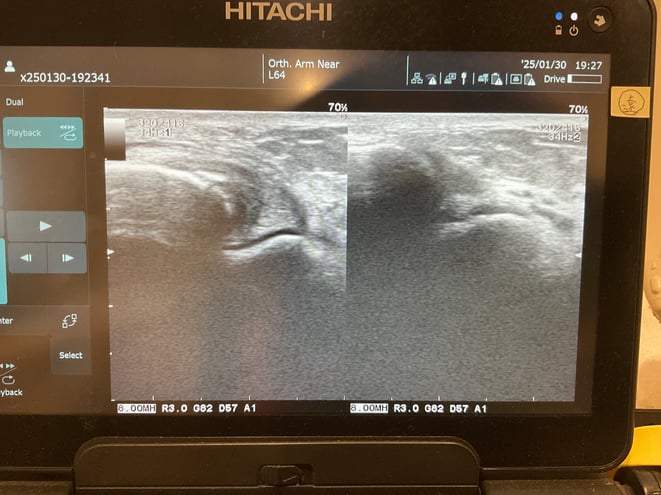

超音波観察機器を用いることで、 靭帯や関節の状態をリアルタイムに詳しく評価することができます 。レントゲンでは分かりにくい靭帯の損傷や腫れの程度、 関節内の状態などを確認し、 正確な患部の観察に基づいた適切な治療法をご提案いたします。